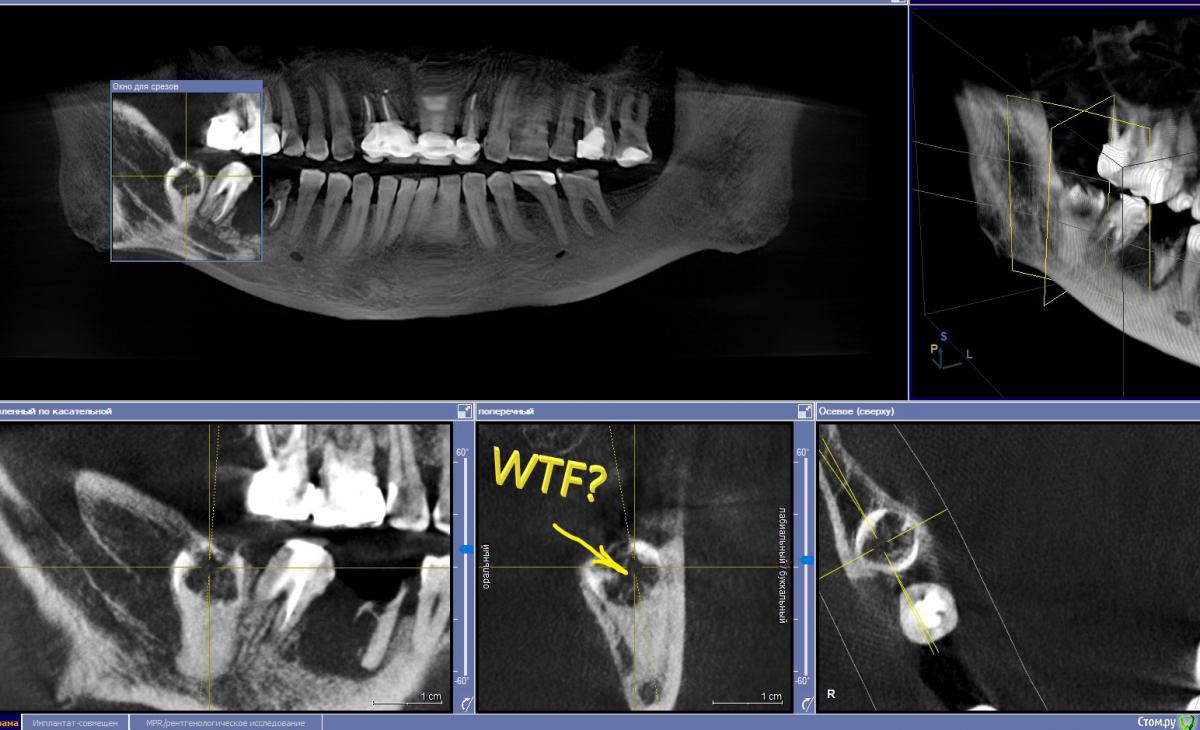

Дмитрий М Опубликовано 16 декабря, 2019 Поделиться Опубликовано 16 декабря, 2019 Коллеги, кто сталкивался? Что произошло с коронкой 8 зуба? полная ретенция, сообщения с полостью рта нет! никогда не беспокоил (пациент и не знал о существовании 8) Ссылка на комментарий

Дмитрий М Опубликовано 18 декабря, 2019 Автор Поделиться Опубликовано 18 декабря, 2019 (изменено) Резорбция или кариес. Удалять планируете?тоже думал кариес, но не кариес 100% резорбцияпланировал удалять, раскрылся и увидел кость в полости зуба, периодонтальной щели нет, как анкилозированный! удалил 6,7,8 не стал, лишняя травма. пульповой камеры нет, зуб мертвый, расти он не будет, имплантации не помешает. Изменено 18 декабря, 2019 пользователем Дмитрий М 2 Ссылка на комментарий